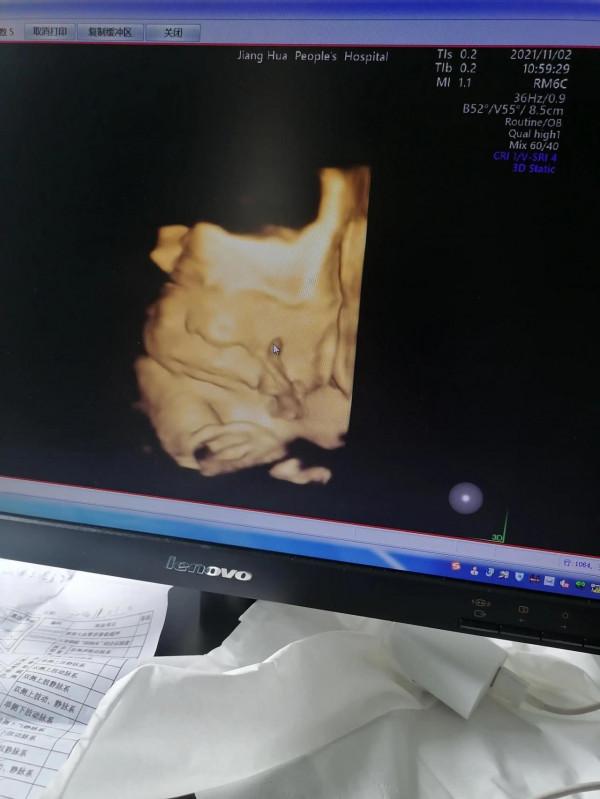

孕30周的四維彩超單,能看出來是男孩兒女孩兒嗎?

昨天去做了二次四維,花了我四百多大洋,真心不便宜。原本不打算做的,因為看了網上很多說八個月因為檢查出身體疾病而引產的,想想還是不放心。自從27周糾結過後決定留下這個孩子,那就希望寶寶能夠健康誕生吧!

看孩子的B超圖片,感覺比我女兒那會兒還醜,鼻子比他姐姐還塌[捂臉] 感覺有點像男孩兒。不過不管是男孩還是女孩,只要孩子健康就行。不過如果是女孩兒的話,就可以省下一大筆買衣服的錢,姐姐的衣服都給你留著呢[呲牙]